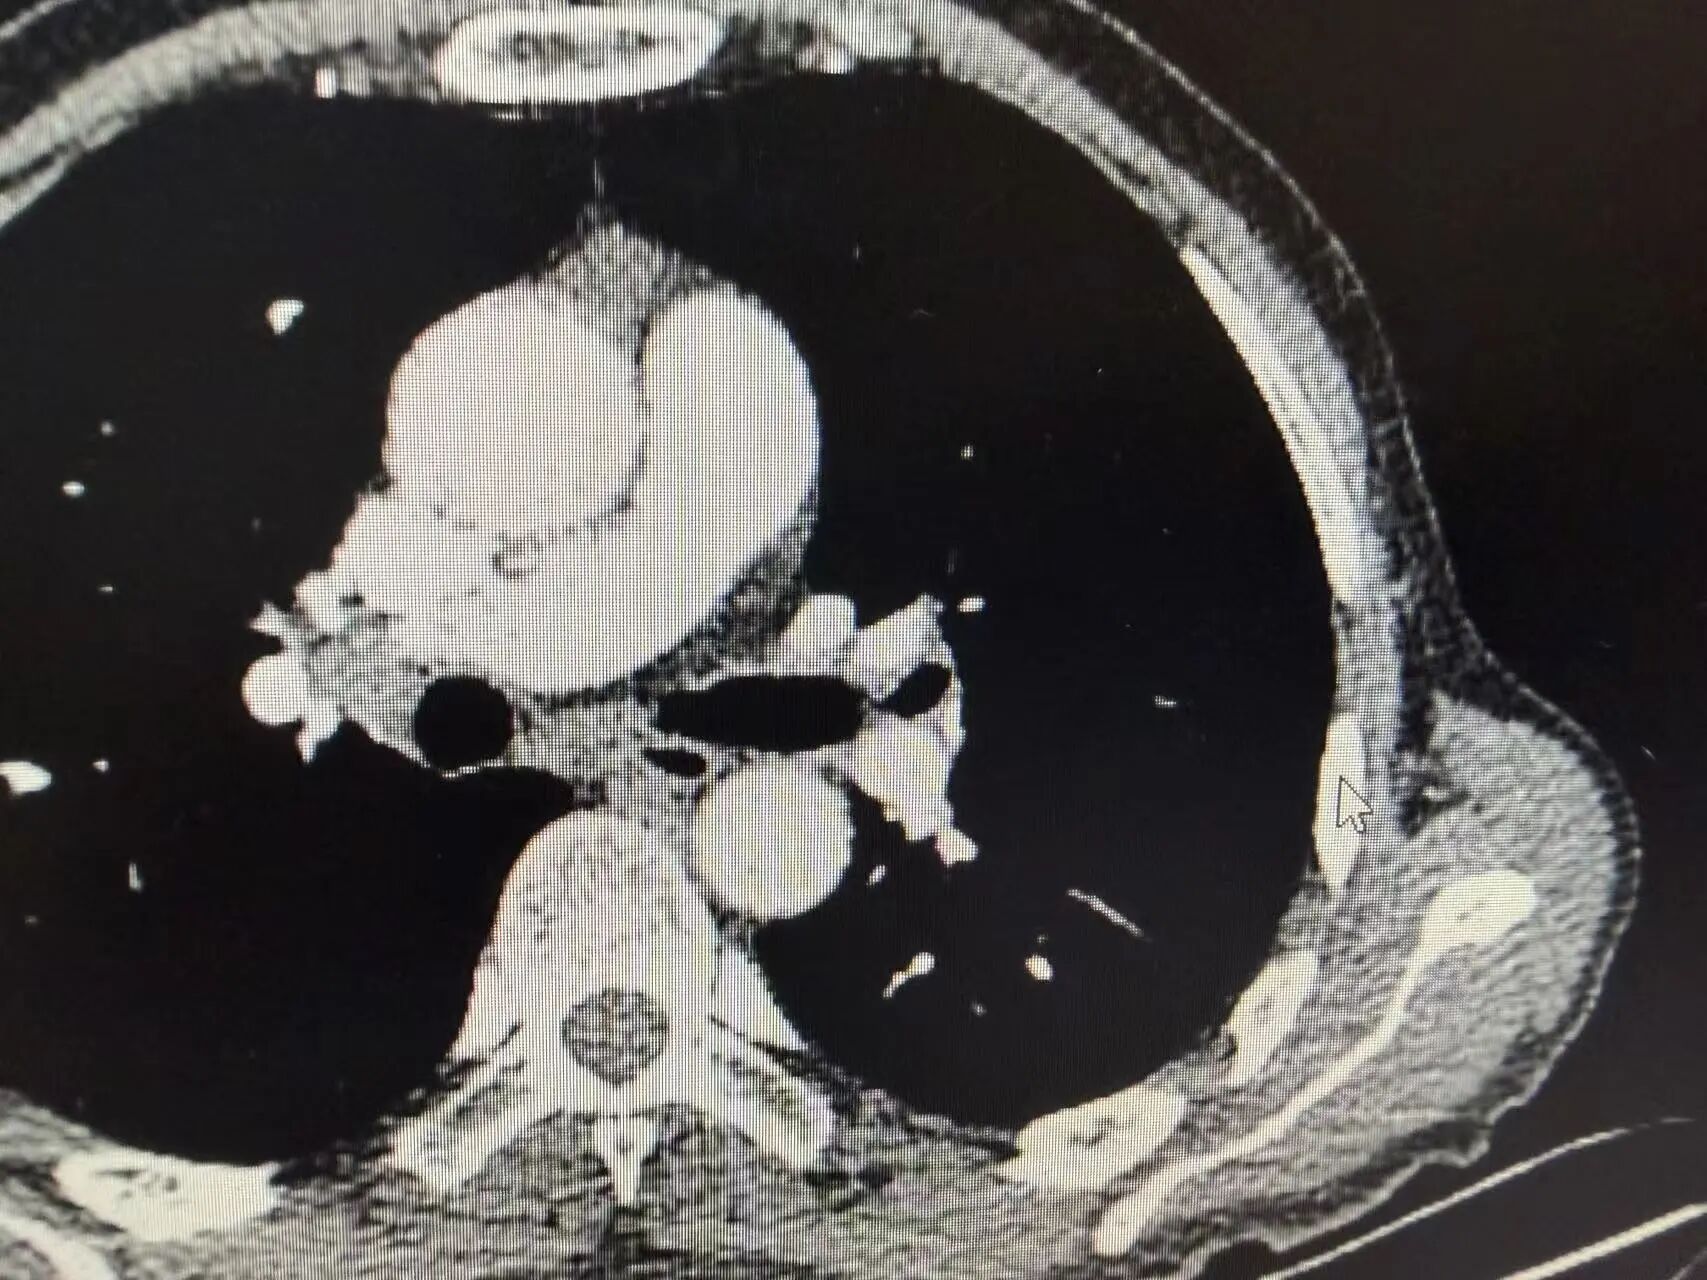

进一步的病理诊断结果明确:王叔患上的是鳞状细胞癌。气管镜检查下,能清晰看到左侧支气管管口被新生物堵塞,肿瘤牢牢“盘踞”在左上肺根部。如果贸然开刀,不仅要切除整个左肺,甚至可能因为肿瘤与血管、支气管粘连过紧,无法实现根治性切除,反而会给患者带来更大的创伤。

1-1.jpg

支气管镜下可见左上叶支气管口新生物